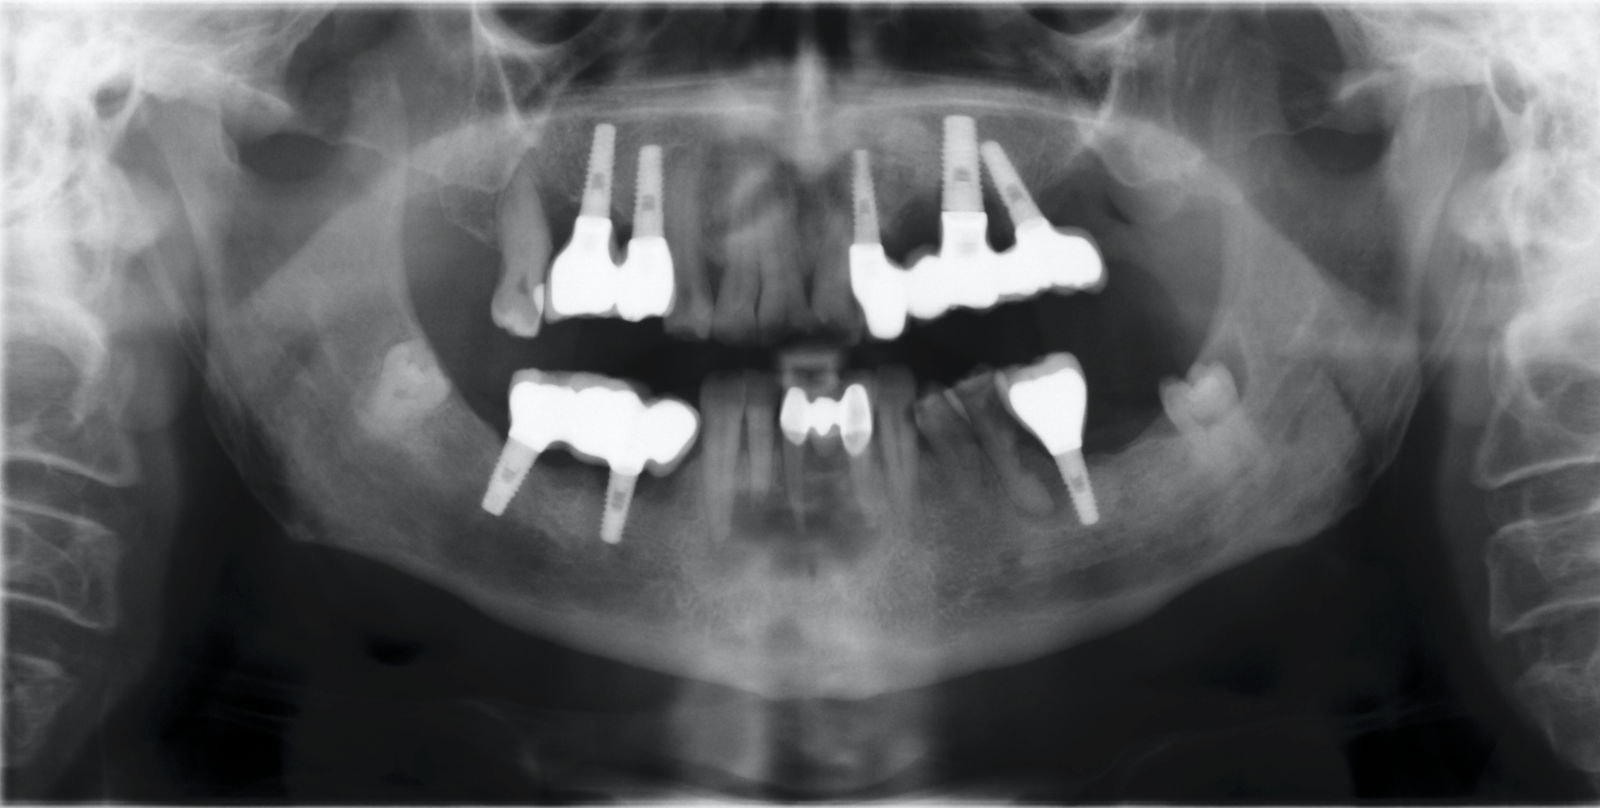

Paciente que comienza tratamiento de implantes en iDental en Enero'16, las prótesis sup e inf terminadas las colocan en Noviembre'17. Adjunto periapicales y fotografías de las prótesis.

La verdad es que la paciente no refiere muchas cosas sobre el caso. Estarán colocados aproximadamente hace 4-5 años quizá algo mas nos refiere. Nunca se llegaron a cargar y [...]